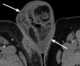

Fournier gangrene

Fournier gangrene is a type of necrotizing fasciitis or gangrene affecting the external genitalia or perineum. It commonly occurs in older men, but it can also occur in women and children. [Source: Wikipedia ]